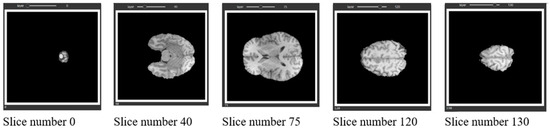

The approach used in this research involved the utilization of the brain tumor segmentation challenge dataset (BraTs 2021). The dataset was publicly released during the MICCAI conference and was subsequently utilized in a competitive setting, allowing the participating groups to evaluate their novel methodologies using this dataset. The BraTs 2021 dataset comprises three-dimensional magnetic resonance imaging scans of individuals. The Hold-Out strategy was employed to partition the dataset into two distinct subsets, namely the training set and the test set. The training set constituted 80% of the dataset, while the remaining 20% was allocated to the test set. Figure 6 shows the instances inside the dataset, along with a visual representation of their corresponding actual states in a three-dimensional space.

Figure 6.

Samples in the dataset.